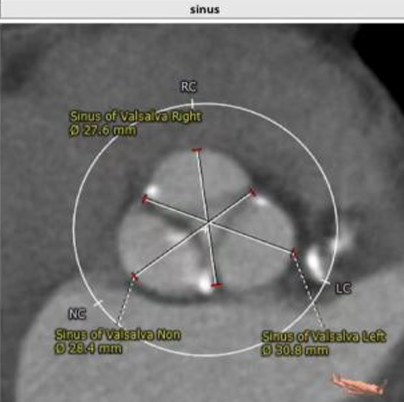

CT

瓣环:20.5mm LVOT:19.2mm

瓣叶分型:三叶瓣 STJ:25.3mm AO:35mm

钙化积分:281mm³

左右冠脉高度:LCA:11.5mm RCA:16.7mm